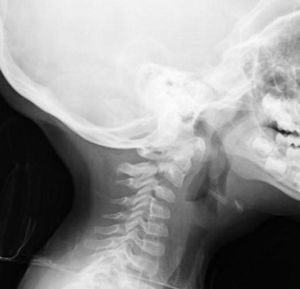

Texto completo La columna vertebral experimenta enormes cambios durante su desarrollo. En los niños, la columna cervical inmadura presenta numerosas variantes de la normalidad que deberíamos conocer para no interpretarlas como patológicas, evitando así realizar exploraciones complementarias innecesarias.

Presentamos el caso de una niña de 3 años que acude a urgencias presentando cervicalgia de 6 días de evolución, sin antecedente traumático y con movilidad cervical activa limitada. La Rx cervical lateral evidencia desplazamiento anterior del cuerpo de C2 sobre el de C3, compatible con pseudosubluxación fisiológica C2–C3 (fig. 1), la variante más frecuente de la normalidad, pudiendo aparecer hasta en el 40% de los menores de 7 años.

Una detallada anamnesis, un riguroso examen clínico y radiológico permiten establecer el diagnóstico la mayoría de las ocasiones.